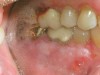

The oral cavity often is affected early in the disease process and, on occasion, may be the only site of involvement.59 Le­sions most often are seen on the buccal mucosa, palate, tongue, and lips. They manifest as quickly bursting blisters, leading to erosions and ulcer formation (Figure 11). Gingival lesions may appear first as isolated blisters or areas of tissue sloughing, but, as the condition progresses, severe DG may occur60 (Figure 12). Nikolsky’s sign is prominent, and lesions sometimes may remain confined to the gingiva61 (Figure 13).

Figure 12  Oral presentation of PV on the gingival.

Figure 12